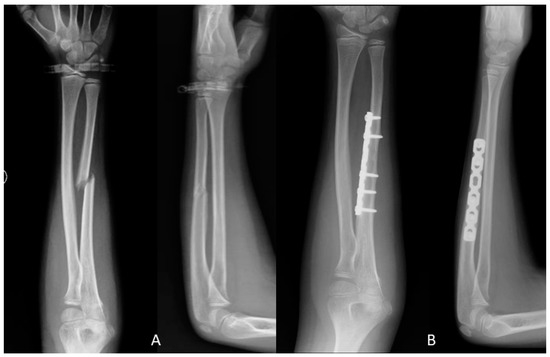

2.2. Surgical Techniques

2.2.1. Open Reduction and Internal Fixation (ORIF)